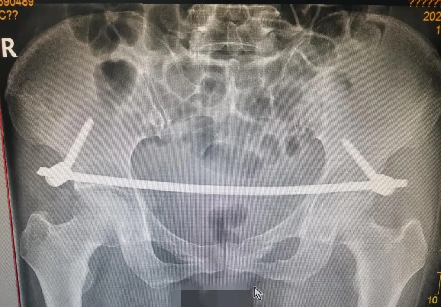

經充分術(shù)前準備,由董明主(zhǔ)任、餘策略主(zhǔ)治醫師、葉強醫(yī)師為患者在全麻下僅用不到2小時便成功完成了手術,術中(zhōng)出血量少,術後第二天患者(zhě)就可以床(chuáng)上坐起及翻身,功能恢複良好。

武寧縣總醫(yī)院人民醫院院區已常規開展骨盆骨折微創術式,以最小的傷害,帶給患者最佳的治療效果,更減輕了患者外出求醫的高昂(áng)經濟負擔。以下是(shì)我院近(jìn)期開(kāi)展的骨(gǔ)盆骨折微(wēi)創治療案(àn)例。